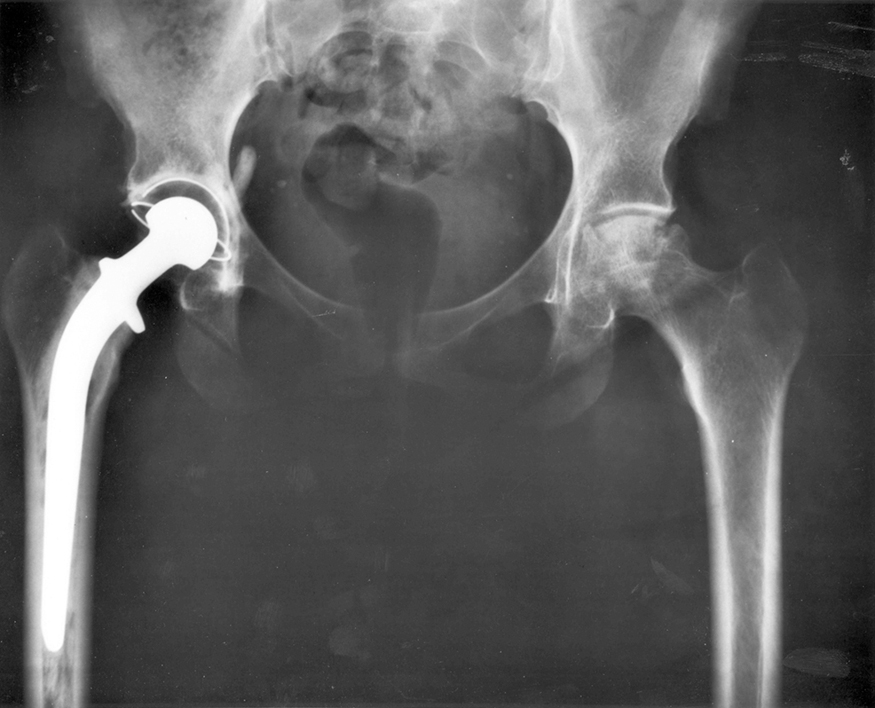

Describe the forces on the hip joint. What means are taken to ensure that this will be a good movable joint? From the photograph (for an adult) in Figure 1, estimate the dimensions of the artificial device.